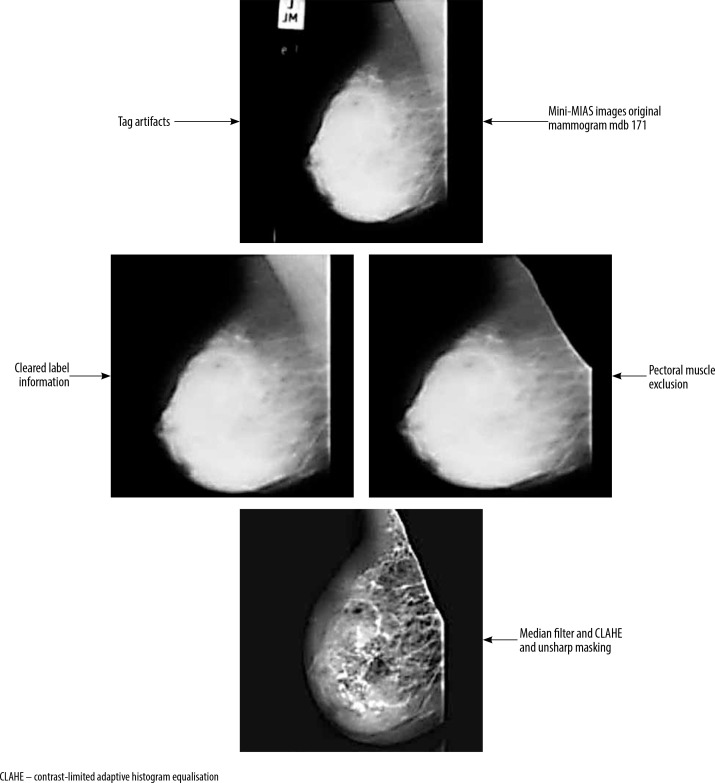

Material and methods: The study utilised the mini-MIAS database of mammography images and examined the impact of applying various preprocessing method combinations to differentiate between malignant and benign breast lesions. The preprocessing steps included removing label information and pectoral muscle, followed by applying algorithms such as contrast-limited adaptive histogram equalisation (CLAHE), unsharp masking (USM), and median filtering (MF) to enhance image resolution and visibility. After preprocessing, a k-means clustering technique was used to extract potentially suspicious regions, and features were then extracted from these regions of interest (ROIs). The extracted feature datasets were classified using various machine learning algorithms, including artificial neural networks, random forest, and support vector machines.

Results: The findings showed that the combination of CLAHE, USM, and MF preprocessing algorithms resulted in the highest classification performance, outperforming the use of CLAHE alone.